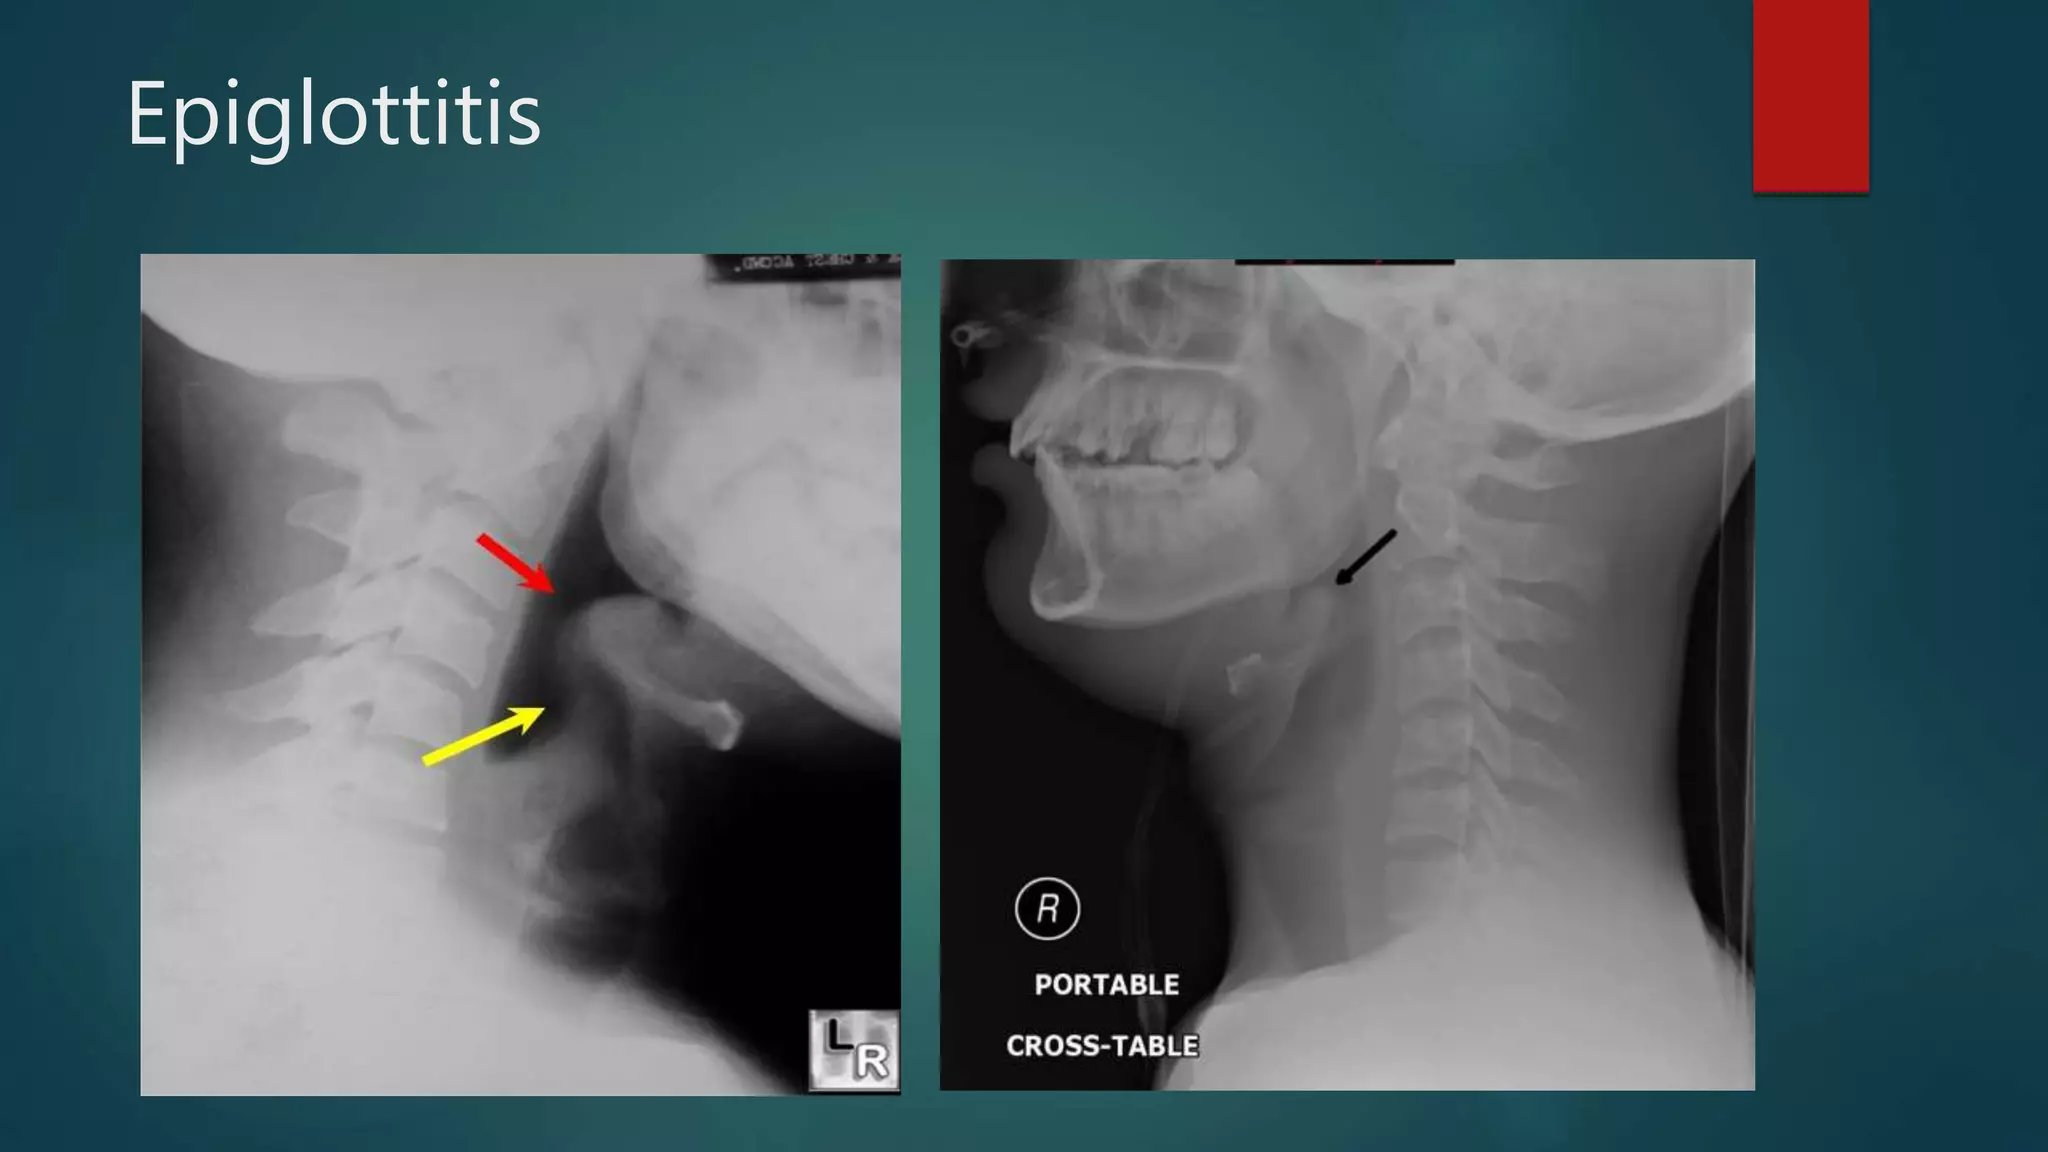

Epiglottitis

• #127 Epiglottitis. Lateral radiograph of the neck demonstrates and enlarged epiglottis (red arrow) and thickening of the aryepiglottic folds (yellow arrow). There is also reversal of the normal lordotic curve in the cervical spine and slight dilatation of the hypopharynx